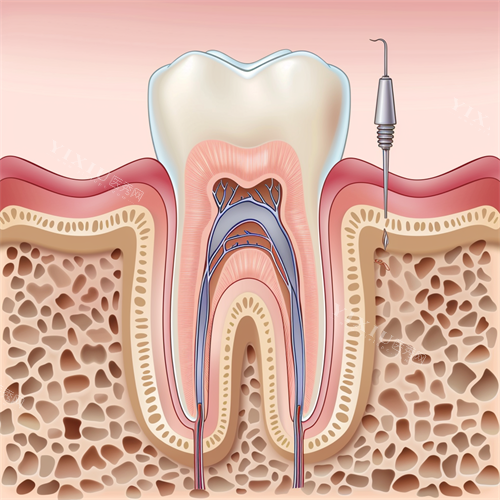

(一)牙髓炎的定义

牙髓炎主要是指发生于牙髓组织的炎性病变。牙髓位于牙齿内部的牙髓腔内,包含神经、血管等组织,当这些组织受到细菌感染、物理或化学刺激时,就容易引发炎症,即牙髓炎。